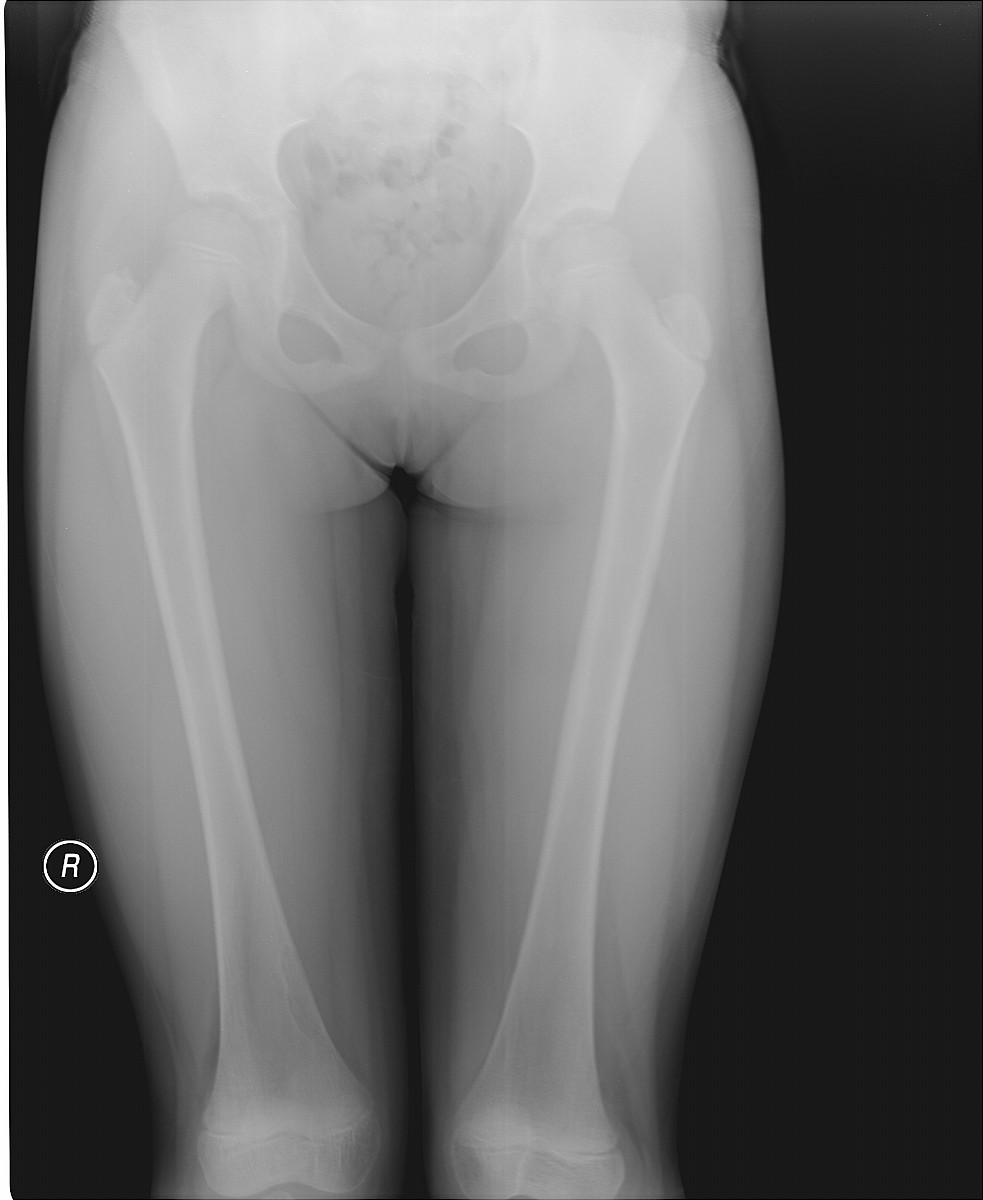

标题: X5349:女,8岁,外伤就诊。右股骨下段内侧皮质下低密度影

女,8岁,外伤就诊。右股骨下段内侧皮质下低密度影考虑什么?图像不太清楚,请大家原谅!

一般考虑为纤维性骨皮质缺损,注意随访与非骨化性纤维瘤区别